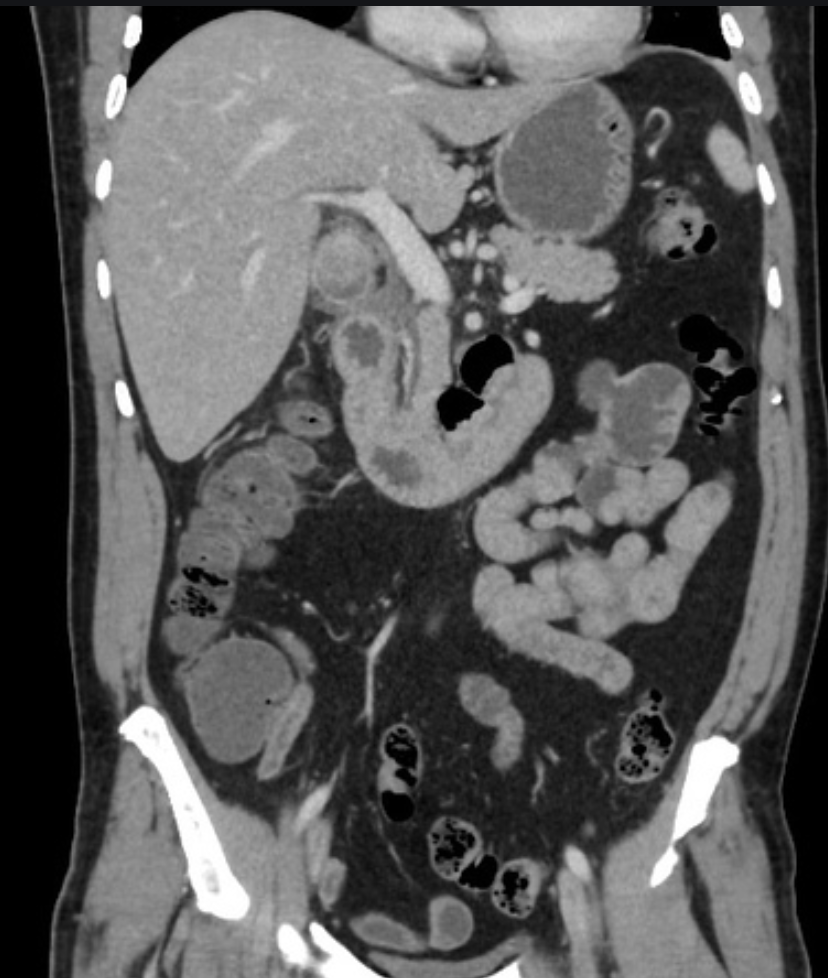

Identify the following structures:

A: liver

B: stomach

C: portosplenic confluence

D: splenic vein

E: pancreatic body

F: SMA